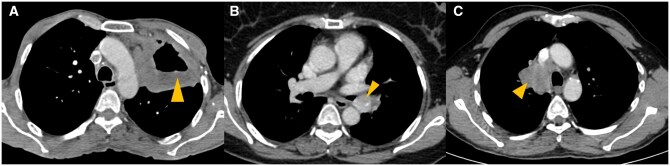

Abstract Image